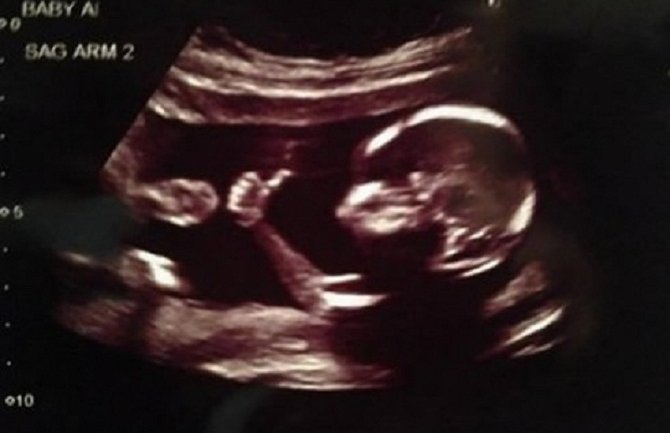

Naime, dečak je držao uzdignut palac, kao da poručuje mami da je sve u redu i da ne mora da brine.

Fotografija je obišla internet, nakon što ju je na sajtu “Redit” objavio oduševljeni budući otac.

Oni koji su vidjeli sliku sa ultrazvuka takođe su primijetili da razigrana beba nije sama. Majka je potvrdila da čeka blizance.